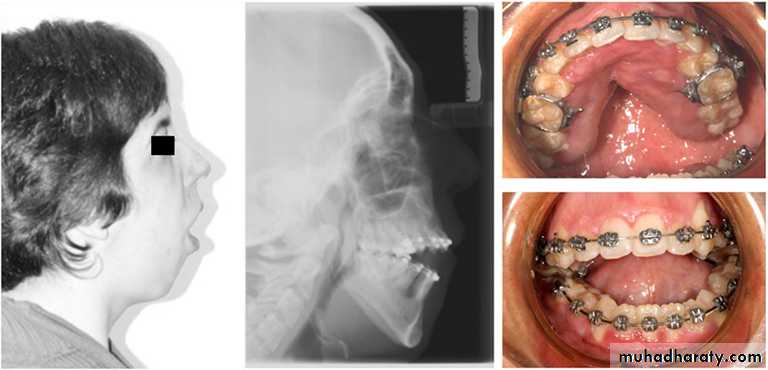

It causes minor teeth irrigularities such as rotation , wear of incisal edge and minor crowding.Mouth Breathing

d. Mouth Breathing: Partial blockage of the nose leads to resistance of airflow and the person shifts to mouth breathingThe blockage occurs due to

• Chronic respiratory infection

• Enlarged tonsils &adenoids

• Nasal polyp

Mouth Breathing

d. Mouth Breathing effects• Over eruption of posterior teeth.

• Open bite anteriorly.

• Increase in overjet.

• narrow maxillary arch.

• Posterior crossbite .

• class II malocclusion.